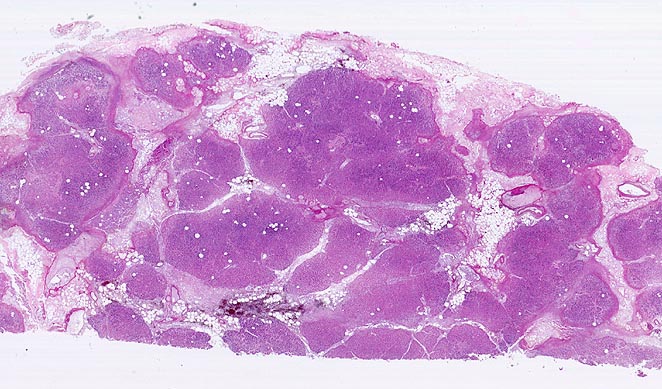

Basel 3BA HS/ Akute Pankreatitis (Kolliquationsnekrose)

Akute Pankreatitis (Kolliquationsnekrose)

• Unregelmässige Nekrosestrassen durchziehen Fettgewebe und Pankreasparenchym.

• Die Grenzen zwischen vitalem und nekrotischem Gewebe sind unscharf.

• Frische, teils hämorrhagische autodigestive Kolliquationsnekrosen von Pankreasparenchym und Fettgewebe demarkiert von zerfallenden neutrophilen Granulozyten.

• Innerhalb der Nekroseareale Ablagerungen von amorphem gelborangem Hämatoidin (eisenfreies extrazelluläres Hämoglobinabbauprodukt).

• Nachweis kokkoider und fadenförmiger Bakterien im nekrotischen Fettgewebe. Das sollte der Kliniker dem Pathologen mitteilen: